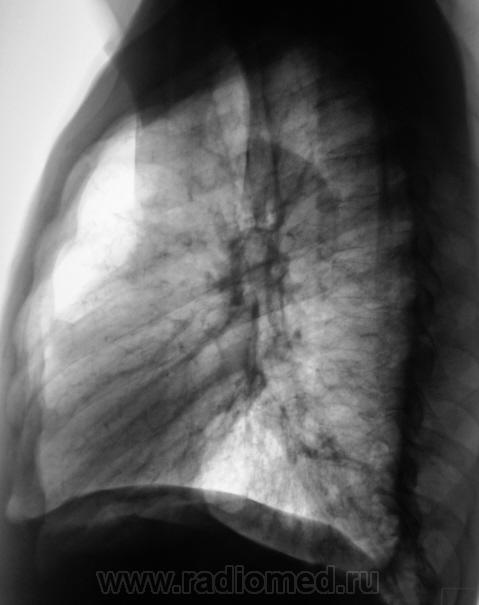

Архива нет. Пациент у нас вообще не проходил. Состоит на учете у "психиатра", очень плохой в плане контакта. После того, как "встал" с томографа, долго отряхивал с ушей "пыль", даже словесный контакт проблематичен.

Да уж показательный случай, 1.как больной на столе то лежал и как выполнял команды "дышать-не дышать".???

Рядом с пациентом стояла его мама и что-то объясняла ему "на пальцах".

Оптимальными оказались срезы 7,0 и 6,5.

С учетом такого расположения образования, можно было бы провести  биопсию тонкой иглой под контролем КТ. А данный пациент куда будет направлен?

Конечно, будет направлен. Наиболее вероятнее в диагностическое отделение ОПТД.

Из ООД пришел периферический.

Был прооперирован в ООД г. Белгорода.

Живет и по настоящее время.